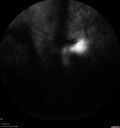

Proliferative diabetic retinopathy with vitreous hemorrhage

53 year old man with foggy vision in the left eye for one day. VA 20/25 OD, 20/40 OS. Diabetes for 10 years. Type II